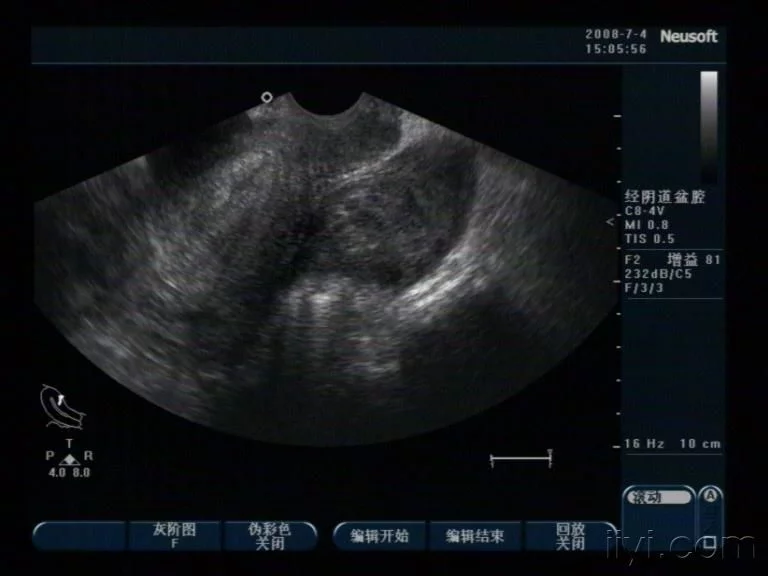

经阴道超声被作为检查附镇早击影察速川久件包块的最常见的影像学手段,主要的局限性在于对癌症缺乏特异性和较低的阳性预测值,尤其对于绝经前妇女,应将经腹部超声和经阴道超声结合起来使用。超声应该对包块的大小和性质(囊性,实性或混合性),单侧或者双侧,有无分隔形成,囊内壁有无结节,有无乳头状赘生物和的入约量玉映溶方备盆腔有无腹水进行描述。

奏架 彩色多普勒超跟声可以测定包块周围的血流情况,可提高二兵备维灰度超声的特异性。在评估盆腔包块的作用仍具有争议主要因为有关于此的报道中良恶性包块的血流测定值如阻力指数,搏动指数,最大收缩期血流速度有一定的重叠。